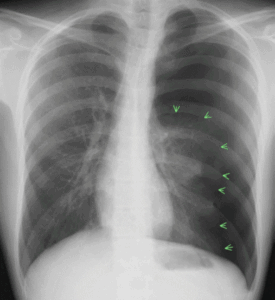

(実際の症例 緊張性気胸 23歳 男性)

突然の左胸痛、進行性の呼吸困難で受診。

胸部X線では、左肺は高度に虚脱し(矢印で囲まれた部位)、左胸腔に溜まった空気が心臓を圧排、心臓が対側に偏位しています。。

低酸素血症もあり、救急車で病院搬送になりました。